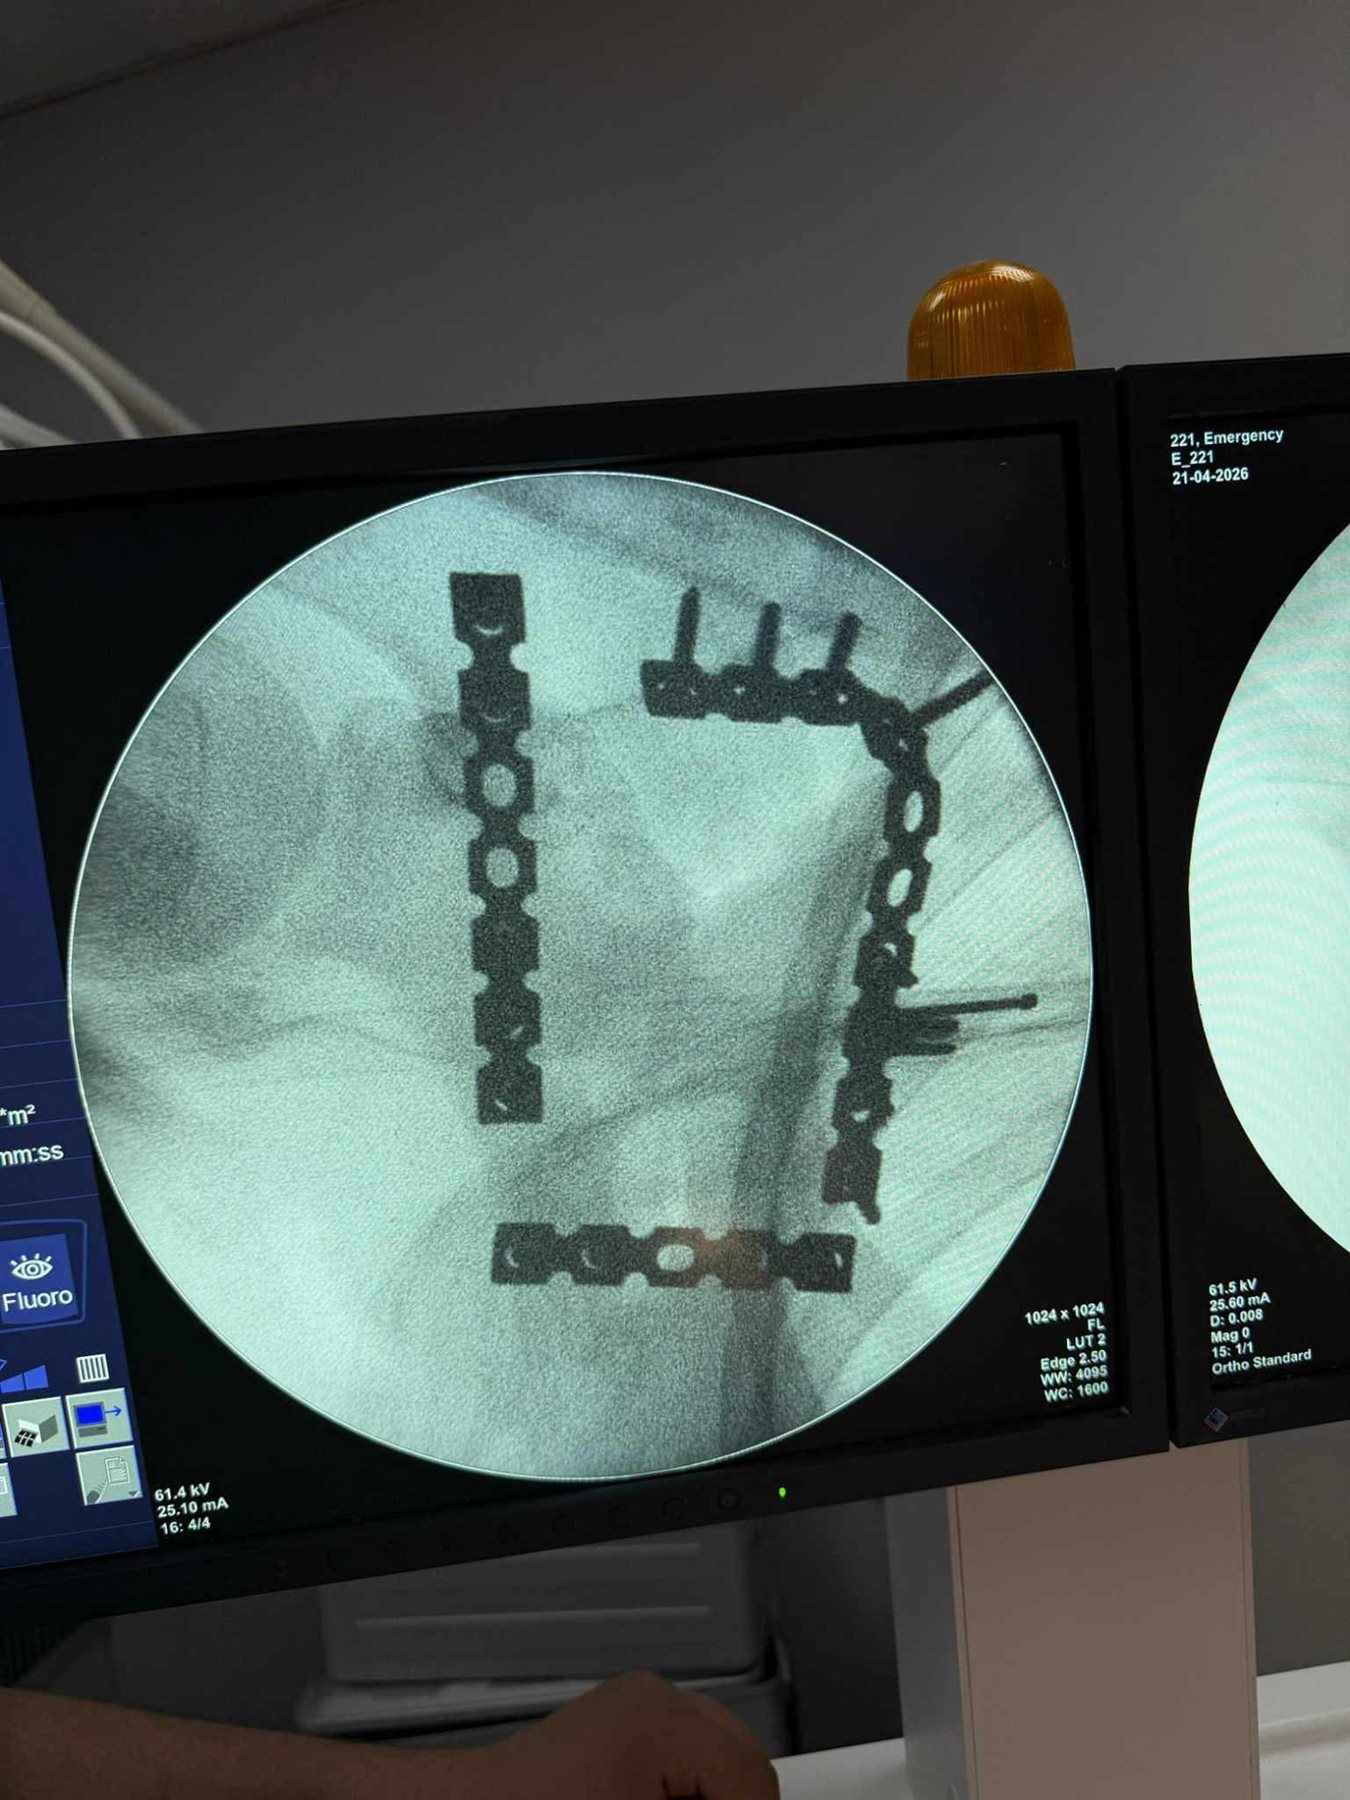

خضع المريض لعملية جراحية معقدة استمرت نحو 4 ساعات تحت تأثير التخدير العام حيث قام الفريق الطبي برد وتثبيت الكسر باستخدام الشرائح والمسامير في اجراء دقيق يتطلب مهارة عالية وخبرة كبيرة خاصة في هذا النوع من الاصابات النادرة.

العملية مرت بنجاح دون حدوث مضاعفات وتمكن الاطباء من تثبيت العظمة بشكل سليم يساعد على استعادة المريض لوظائف الكتف تدريجيا خلال فترة العلاج.